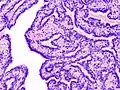

| Histopathology of intraductal papilloma of the breast by excisional biopsy. Immunostaining for p63 protein. | |

Histopathology of intraductal papilloma of the breast by excisional biopsy. Hematoxylin and eosin stain.- Histopathology of intraductal papilloma of the breast by excisional biopsy. Immunostaining for alpha-smooth muscle actin.